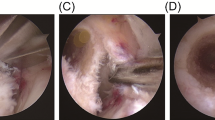

Initially, the first cadaveric knee was used as a model to create different PSI guides until the optimal design was obtained for the correct application in the bone. Subsequently, eighteen 3D-printed PSI (9 for the medial side and 9 for the lateral side) specifically designed for each cadaveric knee (Fig. 1A–D) were printed internally in our center using polylactic acid (PLA) and polyvinyl alcohol (PVA) support with an Ultimaker 3/S5 printer (Ultimaker, Netherlands) by fused deposition modeling (FDM) technology and Ultimaker Cura 4.0 printing software (Ultimaker, Netherlands). During the design and creation of the guide, emphasis was placed on creating small-sized PSI that would fit well to avoid being too aggressive with soft tissue during the surgery. In the design process, a tolerance of 0.4 mm was applied. In this way, the guide fits perfectly into the bone edges, considering any remaining soft tissue.

Lateral approach

A 5-cm lateral incision was performed. Then, the iliotibial band (ITB) was opened, and the approach was distally extended between the Gerdy tubercle and the fibular head. Dissection was performed in this location in the proximal and distal directions, exposing the lateral epicondyle until the FCL and PT femoral attachments were visualized. Then, minimal subperiosteal proximal dissection was performed to allow a correct adaptation of PSI to the femoral bone surface. To achieve this without damaging the remains of the ligament and capsule attachments, the guides were designed and printed allowing 0.4 mm of tolerance. Then, Kirschner wires were introduced across the whole guide. Finally, both tunnels were drilled with lengths of 25 mm and 8 mm in diameter after removing the PSI following the technique described by Laprade et al. [26]. The PSI design had a low profile, so if the position of Kirschner wires was too divergent, it was possible to break the guide in order to keep the Kirschner wires in place.

Medial approach

A longitudinal anteromedial incision of approximately 5 cm was made over the medial epicondyle. The crural fascia was exposed, and a longitudinal incision was made down the fascia. Once the medial femoral epicondyle was exposed, the attachments of the adductor magnus tendon, MCL, and POL were identified. Subperiosteal dissection was performed. Once the PSI was adapted to the bone surface, Kirschner wires were inserted. After removing the guide, bone tunnels were made by a 7-mm drill at a 25 mm in depth, as recommended by some authors [27] (Figs. 2 and 3).